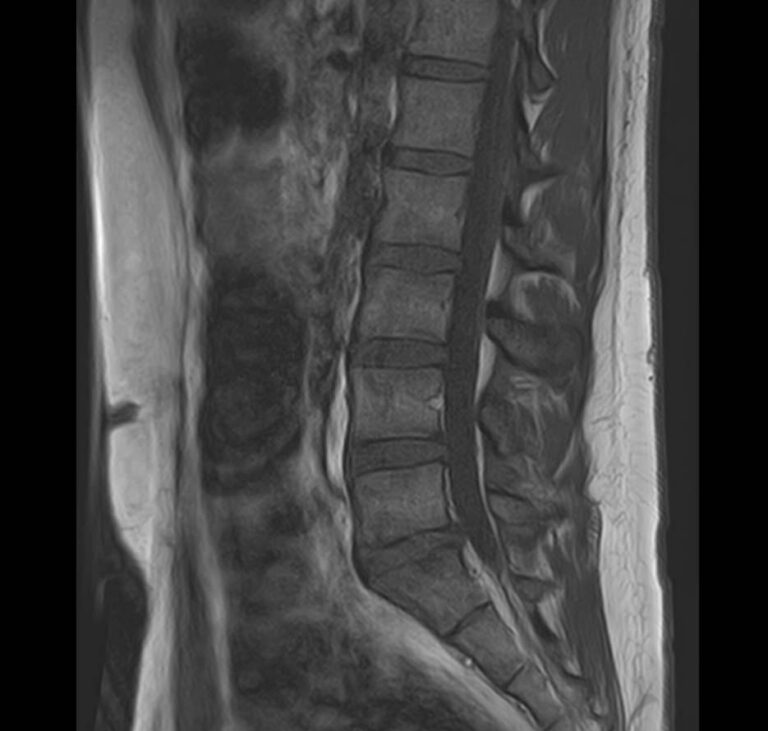

Для диагностики заболеваний ЦНС в клинике «Доступная медицина» проводится комплексное обследование МРТ ЦНС (центральной нервной системы). Клиника укомплектована высокотехнологичным оборудованием, в частности, новейшим 32-канальным высокопольным томографом TOSHIBA VANTAGE TITAN 1,5 Тесла с высокой разрешающей способностью для точной диагностики заболеваний центральной нервной системы.

МРТ центральной нервной системы (ЦНС) (головной мозг + 3 отдела позвоночника)

13 400 / 12 200 руб

Подробнее